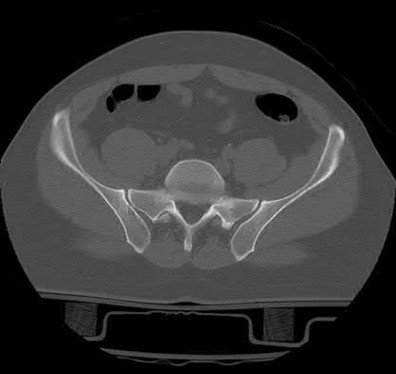

Which of the following images shows an injury pattern most consistent with a lateral compression type 3 pelvic ring injury?

Figure C is an axial CT scan of a lateral compression type 3 (LC3) pelvic ring injury.

Classically, LC3 injuries demonstrate an ipsilateral lateral compression and a contralateral APC (windswept pelvis) fracture pattern. The most common mechanism of injury in these cases is a rollover MVC or pedestrian vs. auto. LC1 injuries are characterized by an oblique or transverse ramus fracture and ipsilateral anterior sacral ala compression fracture, while LC2 injuries consist of a rami fracture and ipsilateral posterior ilium fracture dislocation (crescent fracture). While LC1 injuries can often initially be managed conservatively with protected weight-bearing and close observation, LC2 and LC3 pelvic ring injuries are almost universally operative.

Pennal et al. discuss a radiologic technique for assessing the forces producing pelvic disruption and its use in logically classifying pelvic injury. Based on this radiologic assessment and along with some biomechanical studies, they propose a classification system involving three major forces producing injury that can also be helpful in the management of these patients.

Young et al. performed a retrospective analysis of the plain radiographs of 142 cases of pelvic fractures and identified four patterns of force that presented with distinctive, recognizable radiographic appearances. They describe a classification system for pelvic fractures based on radiographic and clinical findings that correlates with associated injury to soft-tissue structures and enables the surgeon to begin corrective procedures rapidly.

Incorrect Answers:

Answer 1: This represents a lateral compression type 2 injury. Answer 2: This represents a lateral compression type 1 injury.

Answer 4: This represents an anterior posterior compression type 2 injury. Answer 5: This represents an anterior posterior compression type 3 injury.